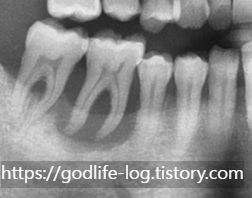

치조골이 소실된 모습

사진을 보시면 치아 뿌리 주변이 하얀 부분이 있고 검게 되어있는 부분이 있죠? 하얗게 되어있는 부분이 치조골이 정상적으로 치아를 감싸고 잘 잡아주고 있는 모습이고 검게 되어있는 부분이 치조골이 상실된 부분입니다. 사진상으로도 저렇게 보이면 이미 치아가 심하게 흔들리는 상태입니다. 이때는 아무리 신경치료를 잘하고 아무리 좋은 보철물로 씌워도 내 치아를 잡아주는 뼈 자체가 없기 때문에 흔들리는 건 없어지지 않습니다. 이미 치아 자체의 문제가 아닌 치아 주변조직의 문제이기 때문에 이런 경우에는 발치를 하시는 게 치료방법입니다. 치조골은 잇몸치료를 한다고 해서 다시 생기는 것이 아닙니다.